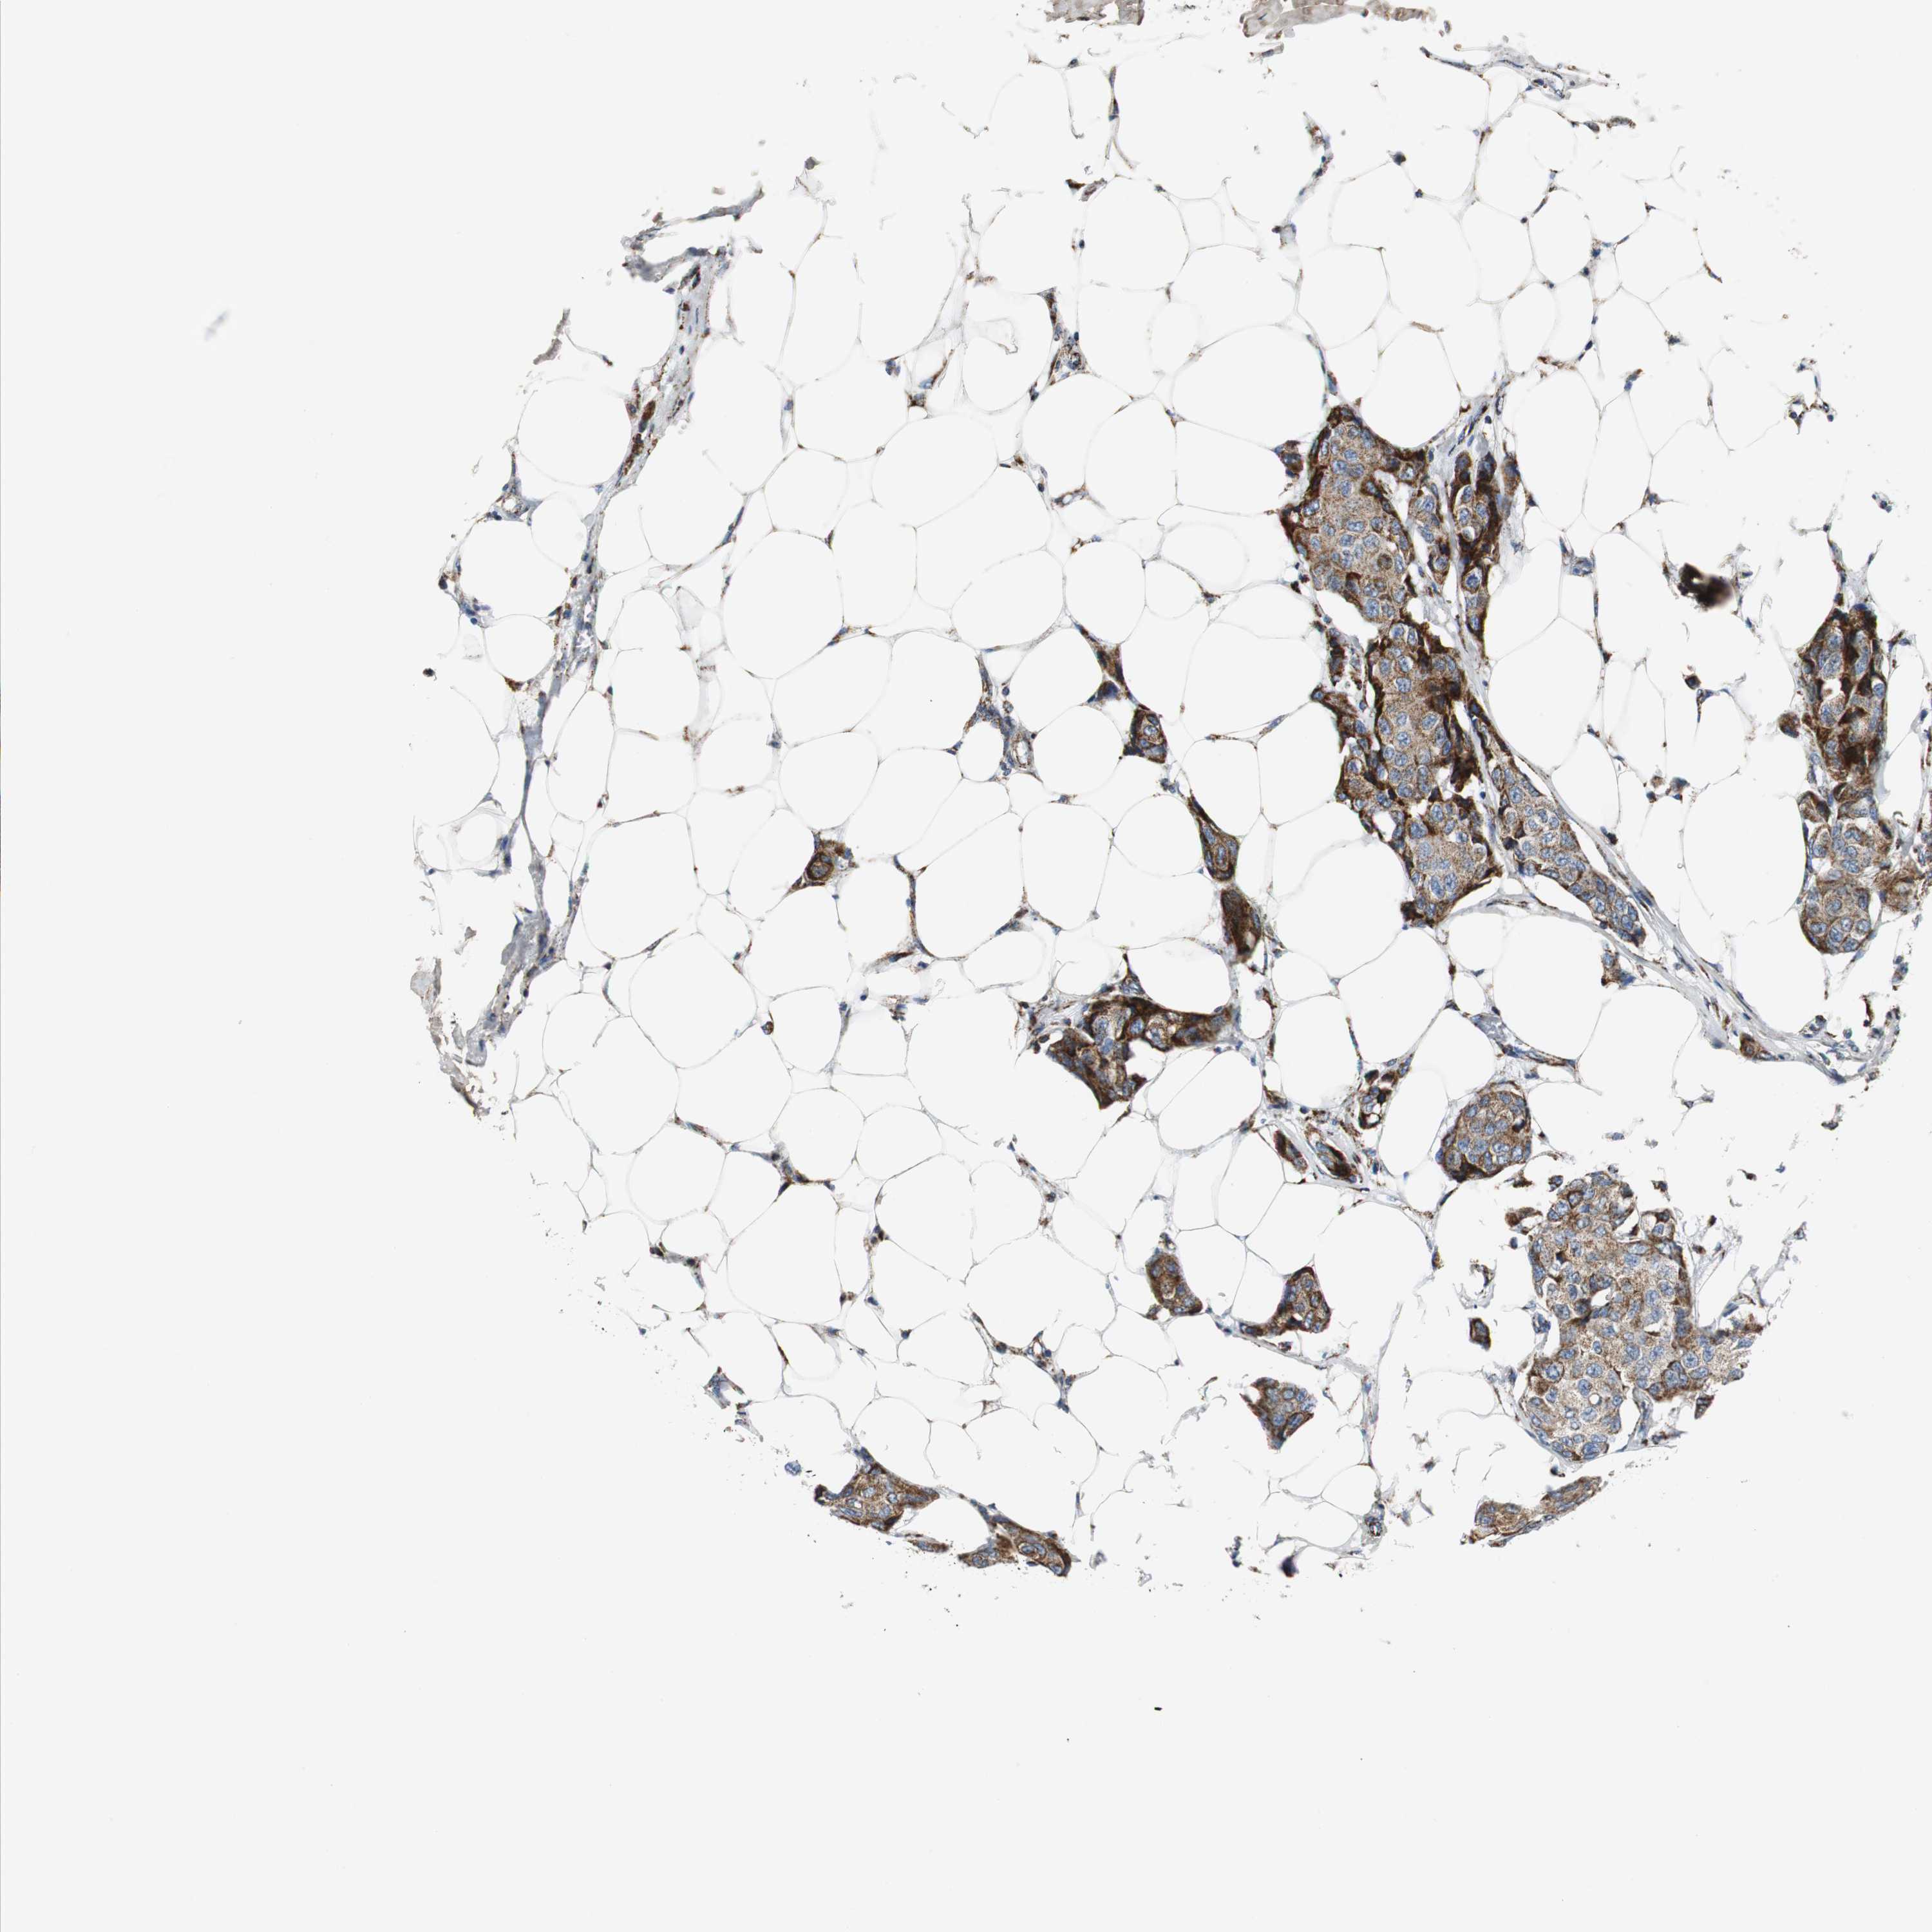

CANCER BREAST CANCER Show tissue menu

BRCA TCGA BRCA VALIDATION PROTEIN EXPRESSION